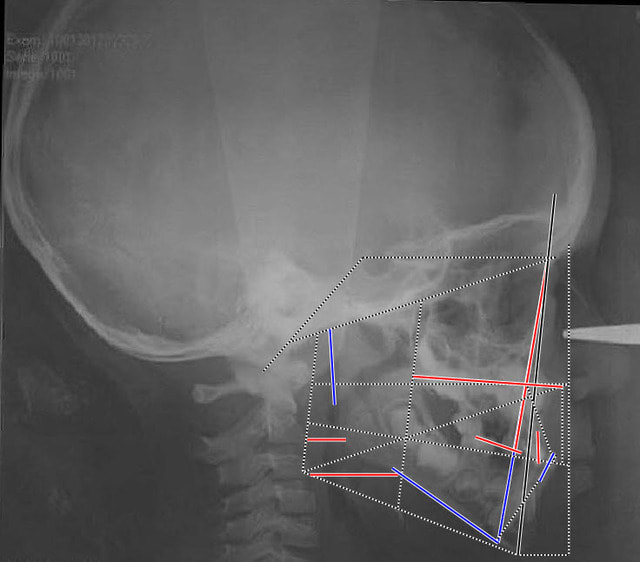

comme un beau schéma vaut plus qu'un long discours voici le tracé architectural du patient.

Cliii trac  architectural pyhqmc - Eugenol